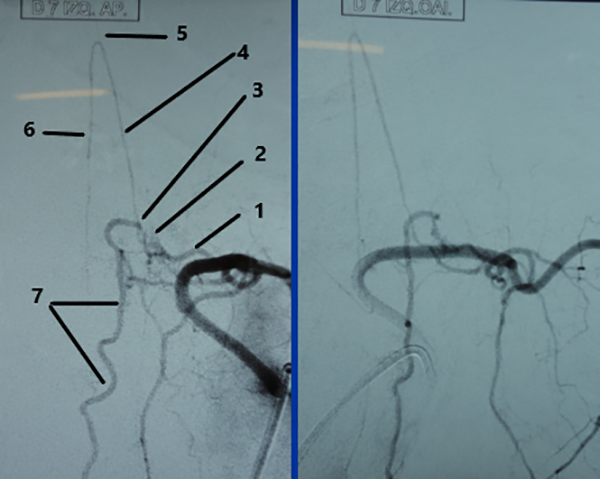

CASO #2. Paciente masculino de 72 años con una historia de 12 meses de parestesias progresivas y ascendentes en ambos miembros inferiores, sin compromiso esfinteriano. Se estudió con RMN (Fig. 9) y una ADM (Fig.10) que muestra una FDAVE en D7 izq. en coincidencia con el origen de la arteria de Adamkiewicz. Fue derivado para microcirugía (Fig. 11). La evolución postoperatoria fue sin déficit neurológico llevando 108 meses libres de enfermedad.

Figura 10: Caso #2. ADM preoperatoria en AP y OAI. La misma arteria radiculomedular D 7 izq. (1) da origen a la arteria de Adamkiewicz (4) y a la FDAVE (2); pie de vena de drenaje (3); horquilla de la arteria de Adamkiewicz (5); arteria espinal anterior (6) y vena espinal posterior (7).